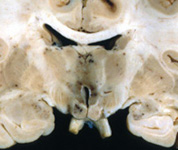

Question 5: A 56 year old man died of gastric carcinoma. The autopsy revealed pathological changes in the brain shown below. The changes are due to:

Incorrect. The pathology (petechiae in the mammillary bodies and around the 3rd ventricle) represents acute Wernicke-Korsakoff syndrome which is caused by Vitamin B1 deficiency.

Correct. The pathology (petechiae in the mammillary bodies and around the 3rd ventricle) represents acute Wernicke-Korsakoff syndrome which is caused by Vitamin B1 deficiency.